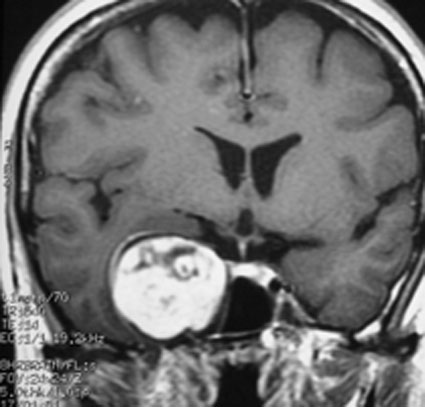

この腫瘍もちょっと大きいので放射線治療だけで治すことは難しいでしょう。この三叉神経鞘腫は少し大きいかなと思うくらいの大きさです。 脳幹部が圧迫されていますから手術摘出した方がいい例です。これも側頭部の前の方の骨を開頭するだけで全部取れます。

これもメッケル腔(ガッセル神経節)という場所から発生した三叉神経鞘腫です。70代後半の女性に見つかったものです。左が2001年,右が2006年です。顔面の軽いしびれだけが症状で13年くらい経過観察していますが,大きくならないし,腫瘍の内部が壊死になってきています。何の治療もする必要のないものです。高齢者の三叉神経鞘腫は自然に小さくなること(自然退縮)があります。